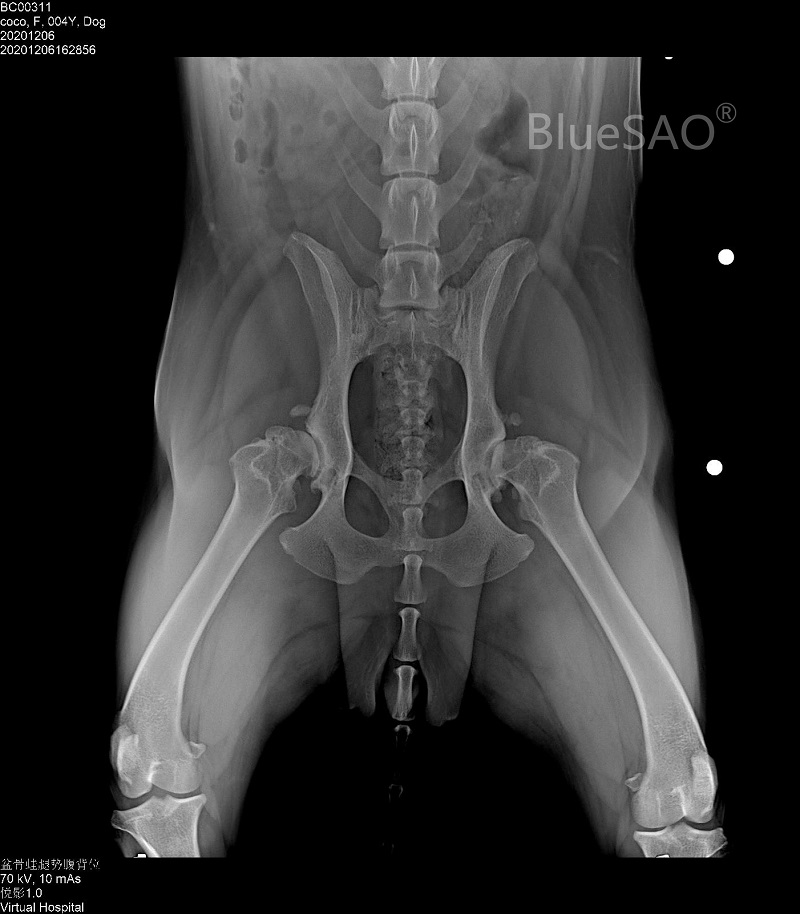

#Dog# #24Months# #35kg# #hip joint-other position-other fracture# #hip joint-other position-THR#

A Labrador retriever, 2 yearsold, female, named Coco, neutered, 35kg. In early 2020, bilateral hip arthritis was diagnosed. At the beginning of December, there was a sudden limp and severe pain in the right hind limb. There was no cruciate ligament injury or other problems. We did THR surgery for right leg by using BlueSAO φ26mmcup,7# stem and φ16mm+6mm head. The surgery was performed jointly by Dr. Zhou Luoping and Dr. Wu Junjie at Shanghai PEACE UNION VETERINARY SERVICE on December 10, 2020.

We did THR surgery for left leg by using BlueSAO φ26mm cup, 7# stem and φ16mm+3mm head. The surgery was performed by Dr. Zhou Luoping on February 1, 2021.